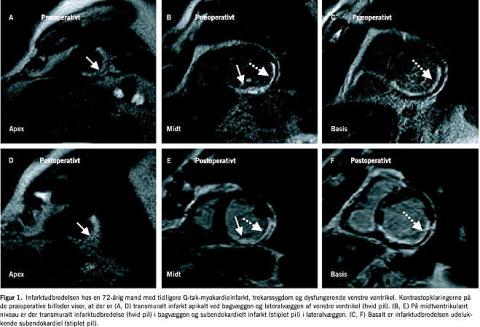

En MR-undersøgelse til påvisning af et myokardieinfarkts udbredelse varer typisk 30-45 min. Undersøgelsen indledes med en vurdering af venstre ventrikels regionale pumpefunktion ved optagelse af dynamiske billeder, såkaldt cine-MR. Der optages typisk 8-10 tværsnit fra basis til apex af venstre ventrikel samt et tokammer- og firekammerbillede. Den regionale funktion af venstre ventrikel gradueres semikvantitativt ud fra en wall motion score for hvert af de 17 segmenter. Herefter indsprøjtes en intravenøs bolusinjektion af ekstracellulær kontraststof (0,2 mmol gadolinium/kg legemsvægt), der inden for et tidsrum på 15-40 min fordeles selektivt til de områder i myokardiet, som repræsenterer arvæv. Gadolinium sænker vævets T1 -værdi, hvilket ved en såkaldt T1 -vægtet skanning viser sig som et område med øget signalintensitet, hvorved det bliver muligt at skelne mellem arvæv og levende myokardievæv (Figur 1 ). Den sene wash-in og wash-out af gadolinium til infarktområder udnyttes således diagnostisk. Det anvendte kontraststof er baseret på grundstoffet gadolinium, som er et stærkt hydrofilt molekyle, der primært udskilles gennem nyrerne (halveringstid ca. 1,5 time afhængigt af stoffets fordeling i det ekstracellulære rum og den glomerulære filtrationsrate). Kontraststoffet har en gunstig bivirkningsprofil, hvor de mest almindelige bivirkninger som varmefornemmelse og metalsmag forekommer hos 1-2%. Anafylaktisk shock og allergiske reaktioner er meget sjældne.

En 72-årig mand med stabil angina pectoris gennem 14 år, blev indlagt i 2001 på grund af pludselig indsættende retrosternale smerter med udstråling til begge arme. Ekg taget akut viste ST-elevation forenelig med inferiort myokardieinfarkt og patienten blev trombolyseret. Ved invasiv udredning med koronararteriografien blev der konstateret trekarssygdom, og patienten blev henvist til aortokoronar bypassoperation. MR-skanning med kontraststof udførtes dagen inden operationen og viste kontrastopladning svarende til, at der var transmural infarktudbredelse apikalt i bagvæggen og lateralvæggen af venstre ventrikel, mens infarktudbredelsen mere basalt i ventriklen var subendokardial (Fig. 1). MR-skannings-funktionsbillederne af venstre ventrikel viste en svært nedsat systolisk funktion. Venstre ventrikels slutdiastolisk volumen udmåltes således til 183 ml og et slutsystolisk volumen på 117 ml, (normalværdien for slutdiastolisk volumen er 115 ml og 36 ml for slutsystolisk volumen) [5], hvilket resulterede i en nedsat global ejektionsfraktion (EF) på 36%. Ved operationen anastomoseredes arteria mammaria til ramus interventricularis anterior a. coronariae sinistrae, der forsyner de forreste to tredjedele af septum interventriculare samt forvæggen af venstre ventrikel. En venegraft anastomeredes til arteria coronaria dextra som forsyner højre ventrikel samt den posteriore tredjedel af septum interventrik ulare og venstre ventrikels bagvæg. En anden venegraft anastomeredes til en margo obtusus gren fra ramus circumflexus, der forsyner lateralvæggen af venstre ventrikel. MR-skanningen med gadoliniumkontraststof fire måneder efter revaskulariserende behandling viste som ventet uændret infarktudbredelse (Fig. 1). Funktionsbillederne af venstre ventrikel viste nu et reduceret slutdiastolisk volumen på 153 ml, og et reduceret slutsystolisk volumen på 96 ml med en global EF på 38%. Regionalt sås en bedret kontraktion ved forvæggen, hvor der ikke var infarkt, samt ved basis af lateralvæggen, hvor infarktudbredelsen er subendokardial. Derimod var kontraktionen ophævet i det transmurale infarktområde apikalt i bagvæggen af venstre ventrikel både før og efter revaskulariserende behandling (Figur 2 A og B ).